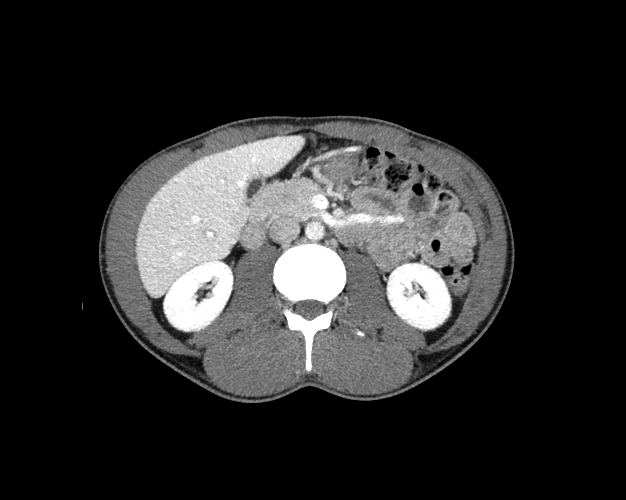

Body

Covers abdominal CT anatomy.